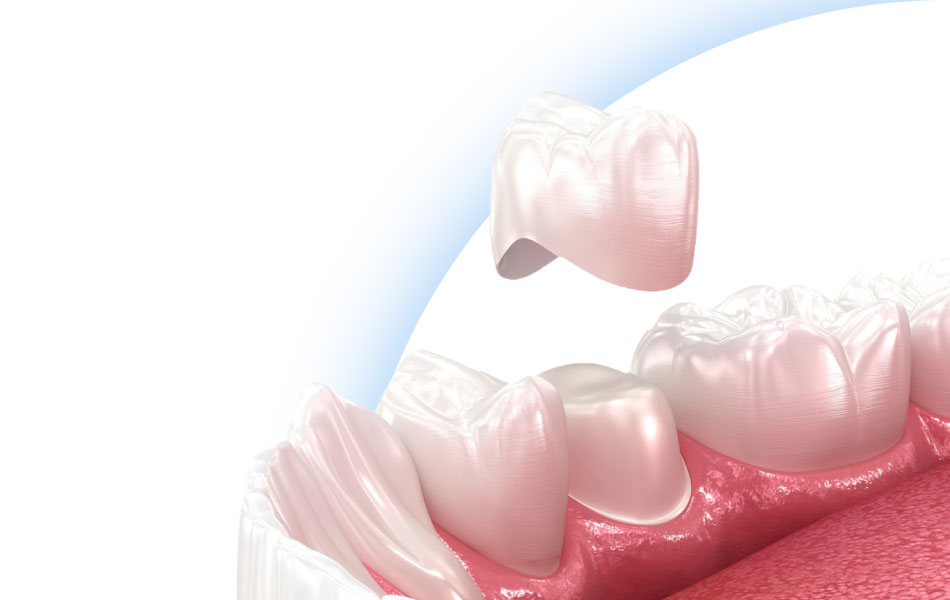

К микропротезам относят адгезивные мостовидные конструкции и протезы «бабочка», виниры ортопедические и терапевтические, керамические и металлические вкладки и пр. Микропротезы изготавливают в зуботехнической лаборатории, поэтому они идеально «садятся» на зубы, а их форма и оттенок соответствуют натуральным зубам.

Качественные и грамотно установленные микропротезы естественно выглядят, их форма соответствует форме натуральных зубов, а краевое прилегание хорошее. Для того чтобы получить микропротезы отличного качества необходимо выбрать надежную клинику, где работают квалифицированные ортопеды и зубные техники.